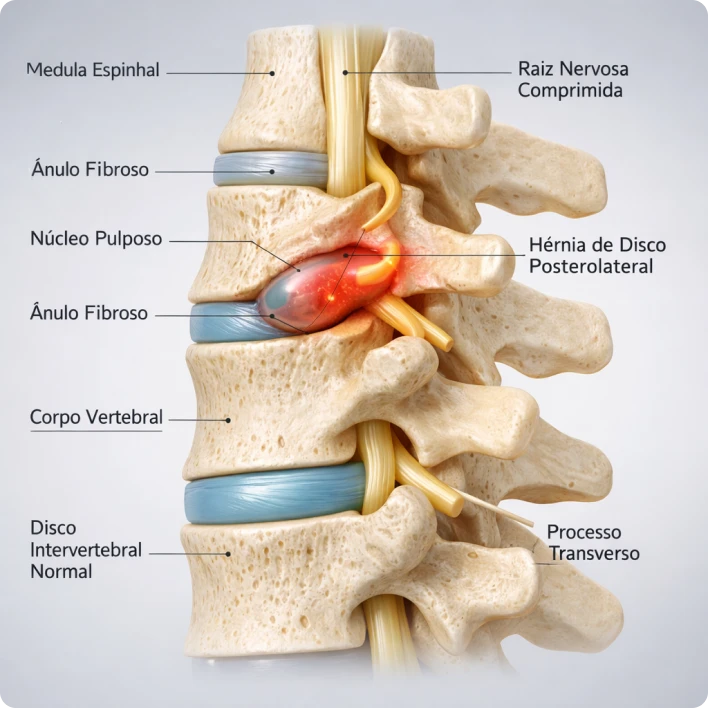

Mas o que é Hérnia de Disco afinal?

A hérnia de disco acontece quando o disco que fica entre as vértebras (aquele "amortecedor" da coluna) se desloca ou rompe, podendo comprimir nervos ao redor.